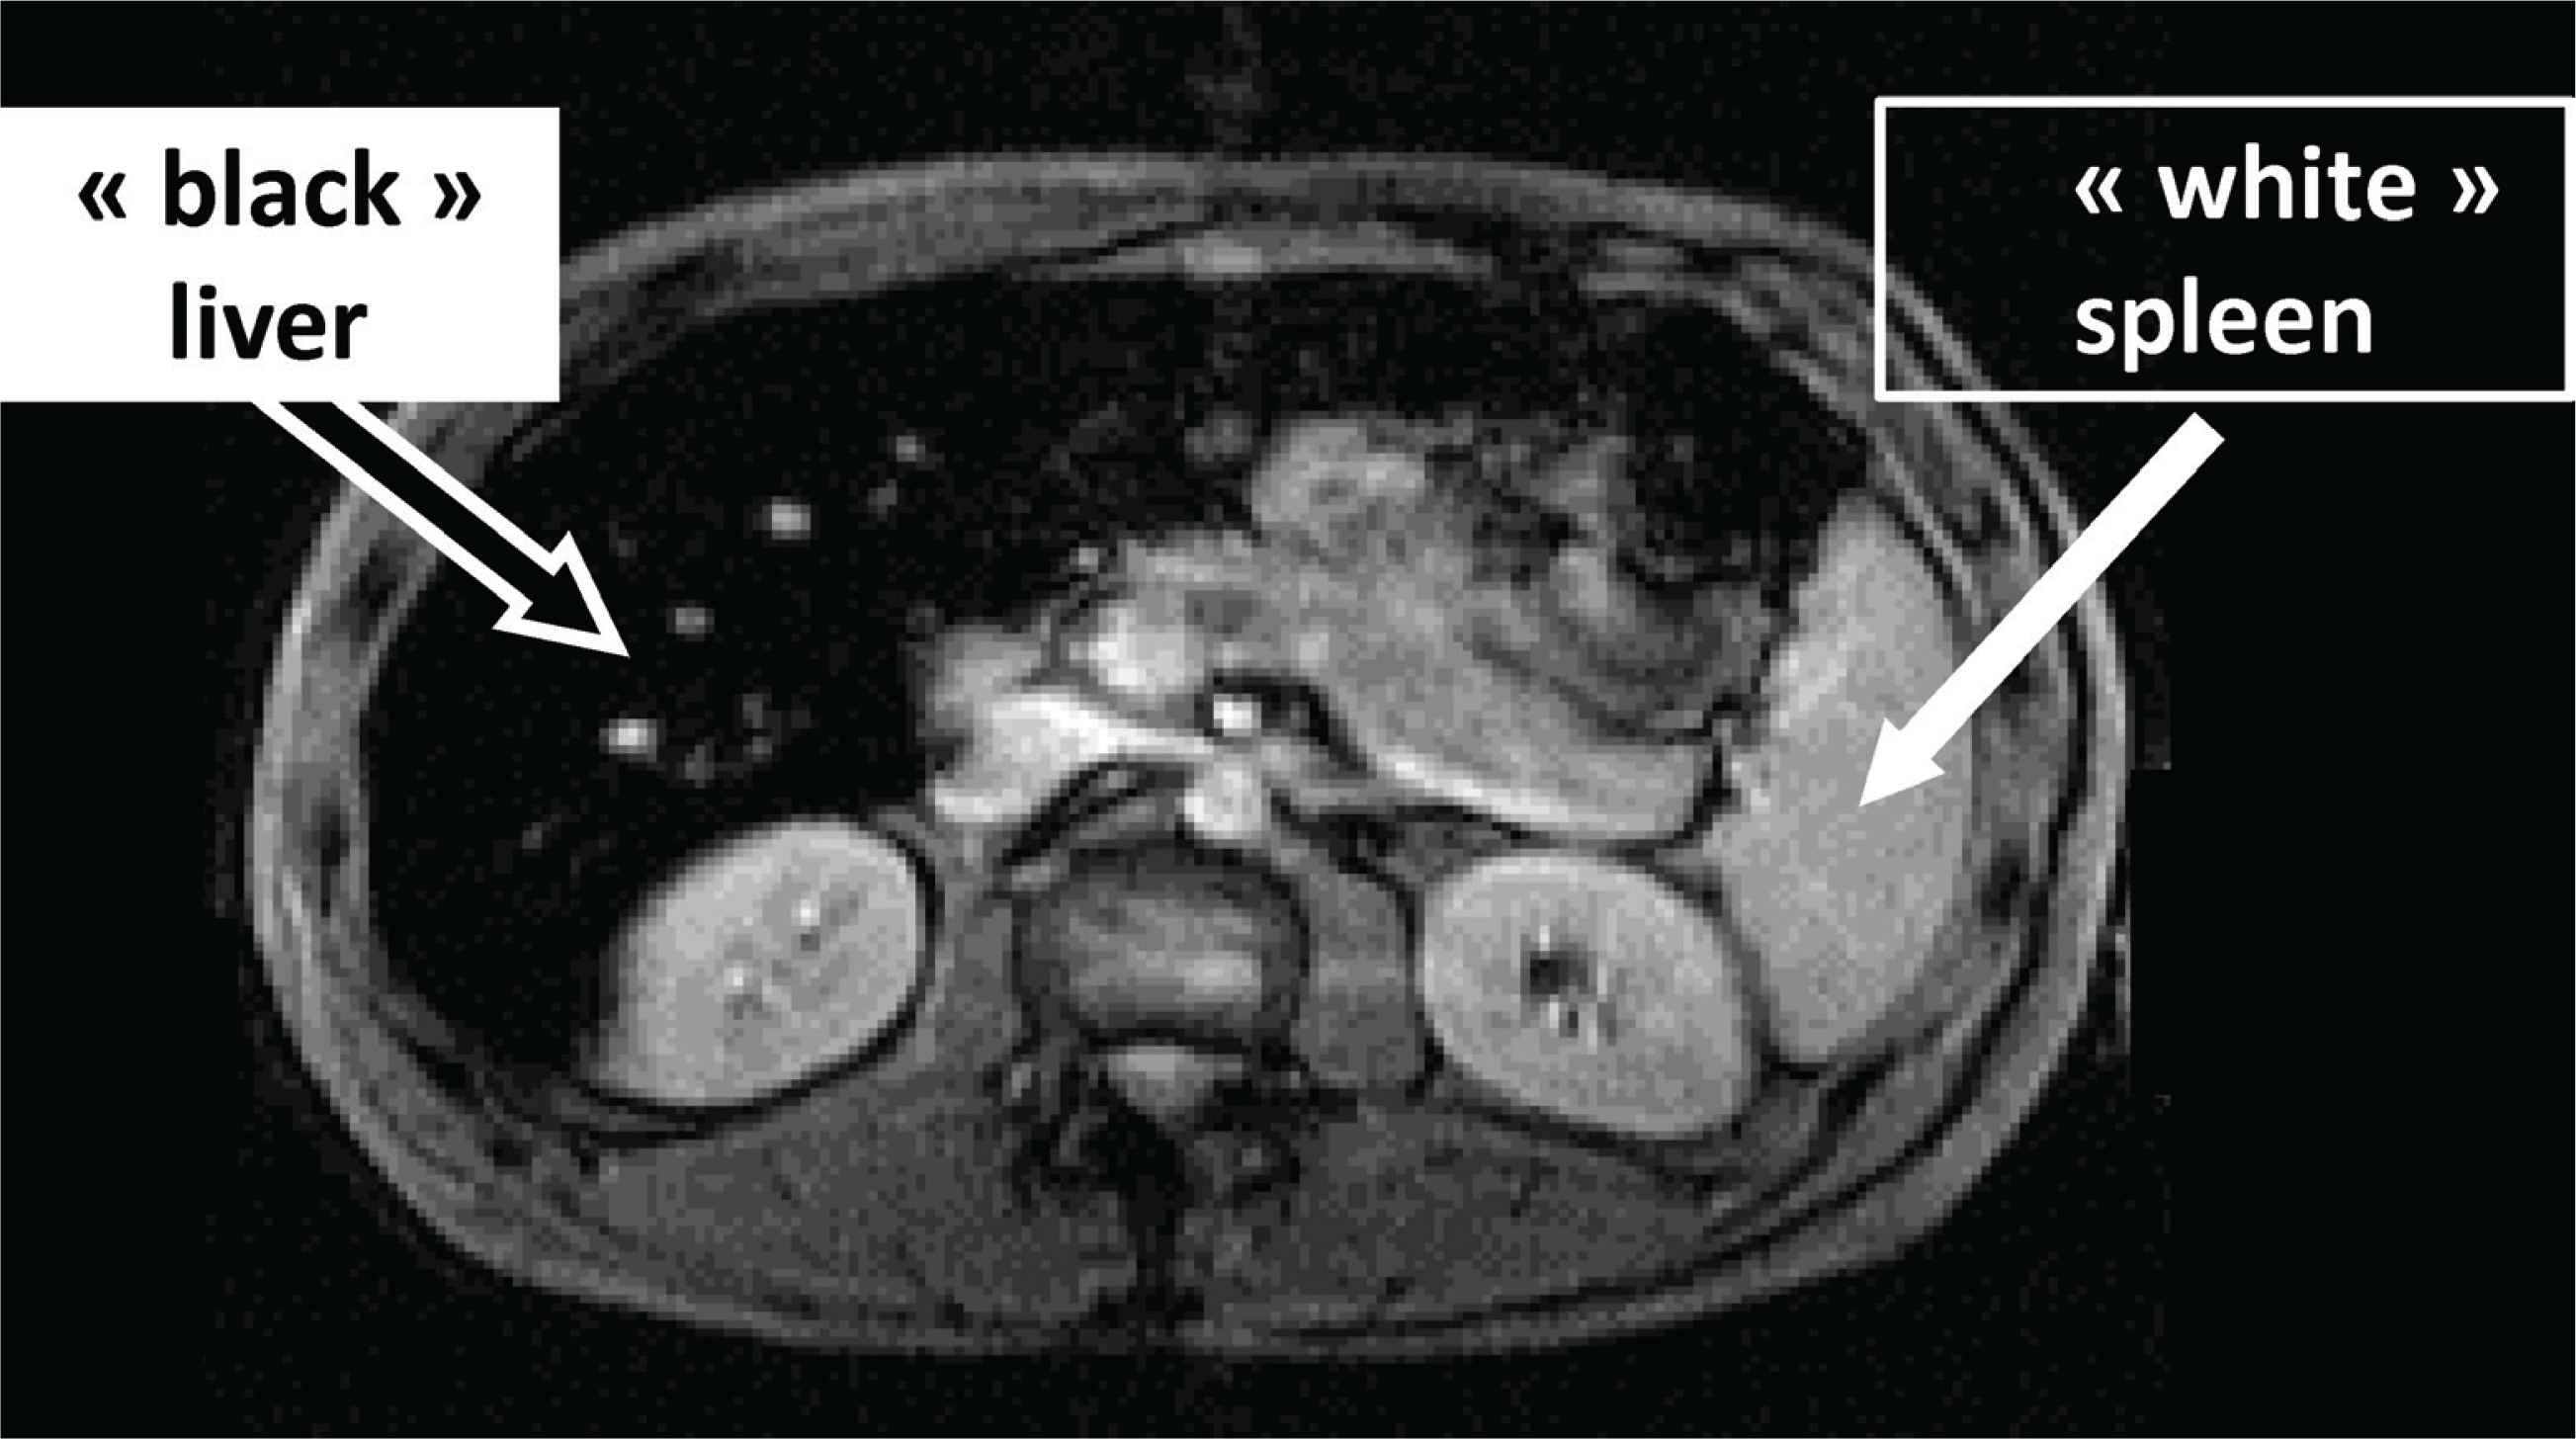

The input of magnetic resonance imaging (Iron-MRI) has revolutionized the diagnosis of iron overload [17]. In the case of hemochromatosis, it presents a triple interest: (i) to visualize hepatic iron excess (iron decreasing specifically the MRI signal); (ii) to quantify this excess (the darker the liver, the higher the hepatic iron concentration); (iii) to provide an important clue for the mechanism of iron overload by assessing the respective hepatic and spleen iron load. Thus, in hemochromatosis, the typical picture will be the contrast between a “dark” liver (“black” if iron excess is massive) and a “white” spleen (Figure 3).

Typical magnetic resonance imaging in hemochromatosis (massive hepatic iron overload contrasting with ‘non-overloaded spleen’).